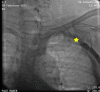

Figure 1

A contrast venogram of the left upper limb showing obstruction of the subclavian vein.